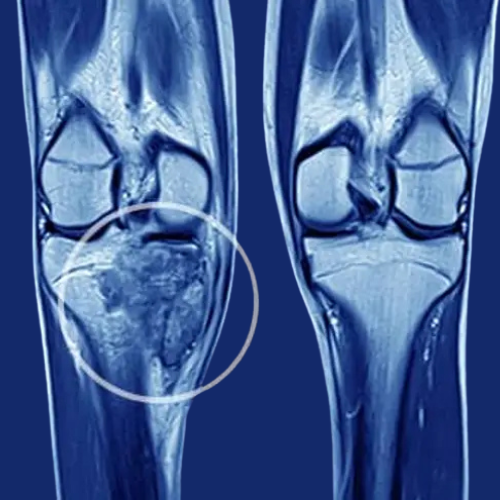

Knee pain due to knee arthritis can severely impact your daily life, making it difficult to walk, climb stairs, or even sleep comfortably. At Dr... Read More